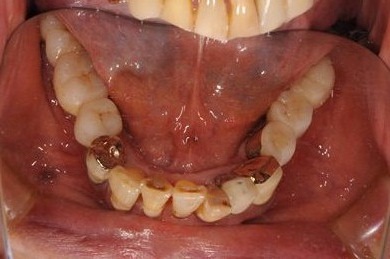

抜歯即日スピードインプラント治療+インプラント除去+セラミック治療

| 主訴 | 20年前に入れたインプラントの周囲が腫れて気になっている。左下の一部治療後の歯が欠けている。 | ||||||||||||||||||||||||||||||||

| 治療内容 | インプラント5本(抜歯即日スピードインプラント)、ハイブリッドセラミック9本(セラミック用土台2本)、メタルボンドセラミック2本(メタルボンド用土台1本)、インプラント除去1本 | ||||||||||||||||||||||||||||||||

| 総治療費 | 2,514,645円 | ||||||||||||||||||||||||||||||||

| 治療期間 | 1年11ヶ月 |